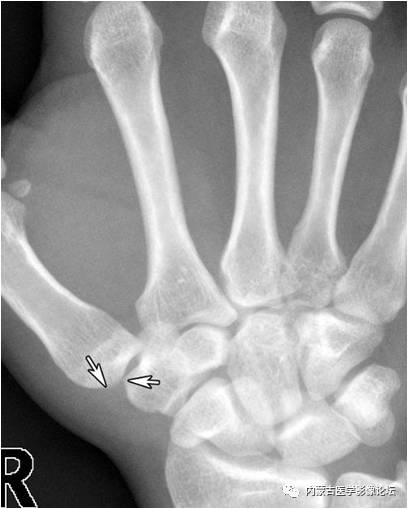

拇指籽骨:拇指指间关节籽骨(箭)较小且略呈三角形,与拇指掌指关节籽骨(箭头)不同,勿误认为撕脱骨折。